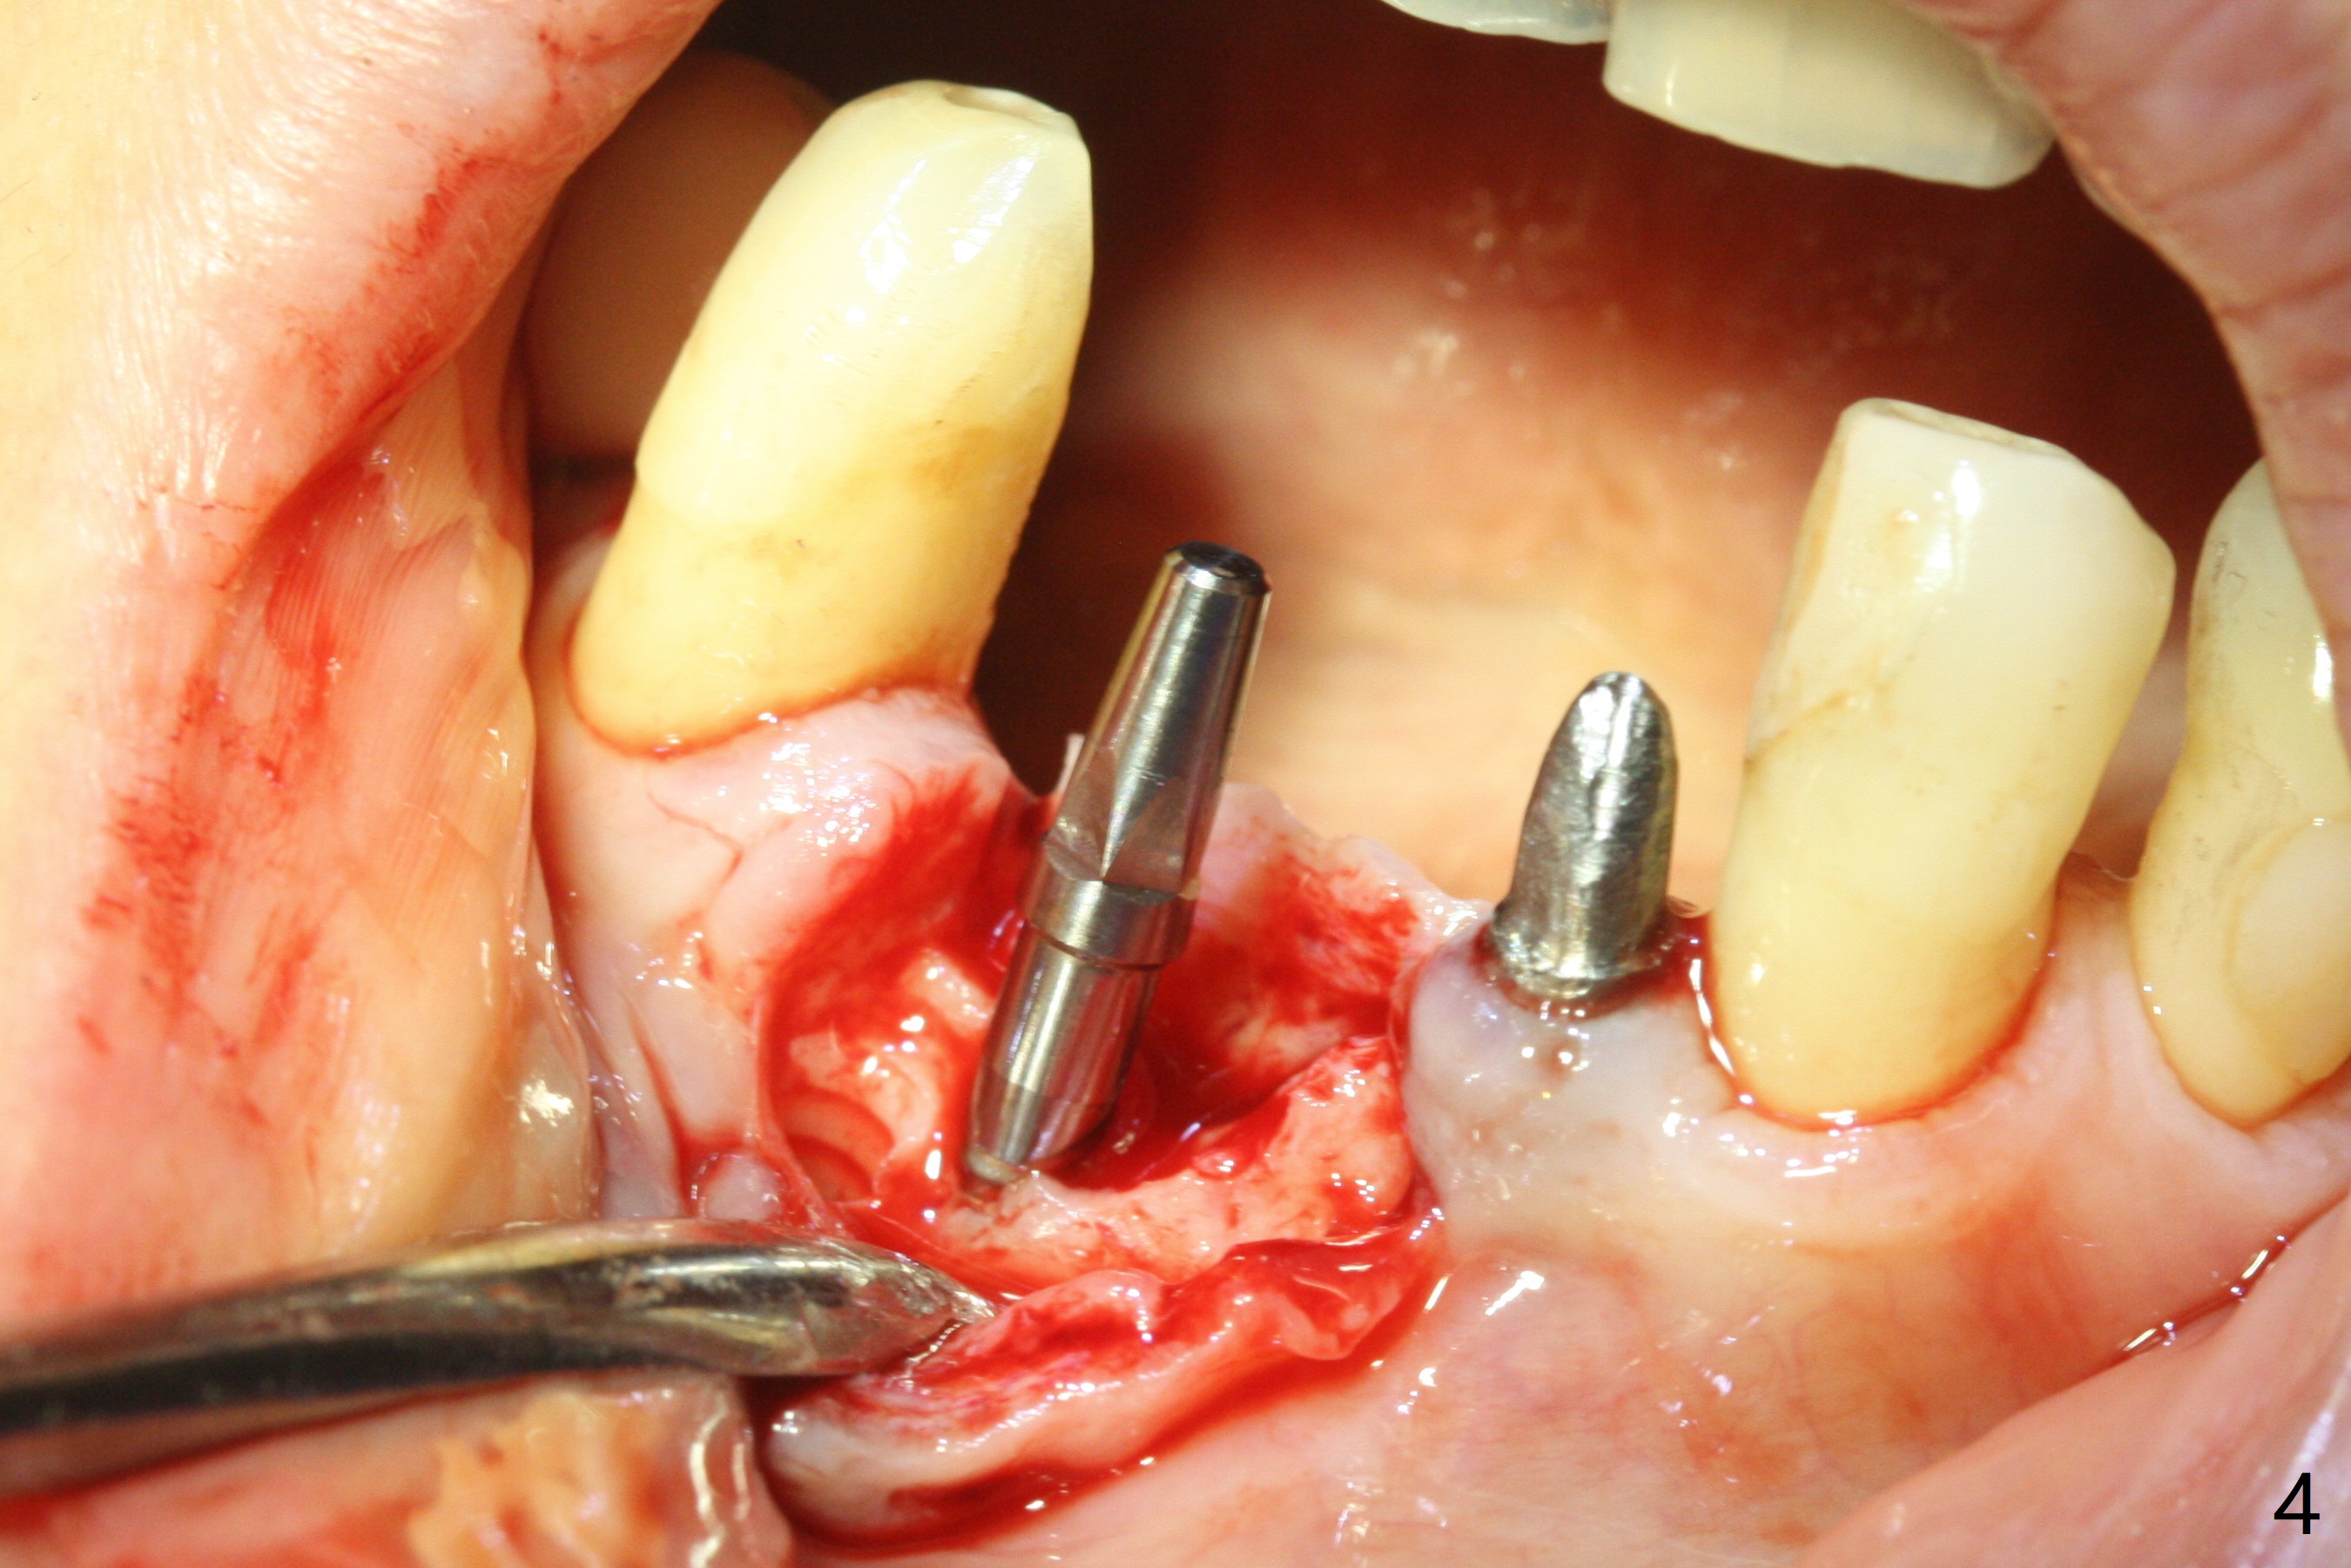

After removing #23-26 FPD and the 3x14 mm 1-piece implant at #26 (Fig.1,2 *), a new osteotomy is initiated in the narrow ridge (after ridge top reduction) approximately at #25 (Fig.2 <). Following placement a 2x10(4) mm implant at #25 (Fig.3-5) and Osteogen plug in the osteotomy at #26, Vanilla graft is placed around the implant, especially buccal. Periodontal dressing is applied after suturing. The buccal and lingual flaps are erythermatous and edematous without pain 8 days postop (Fig.6). The wound seems to be healing 2 weeks postop (Fig.7), no sign of osteonecrosis. With placement of a 2 mm implant at #25 (Fig.8 (>: bone graft buccally)), the buccal plate remains normal in thickness. When a 3 mm implant is placed at #23 (Fig.9), approximately 4 threads appear to be exposed (between arrowheads), partially due to the thick lingual plate (*).